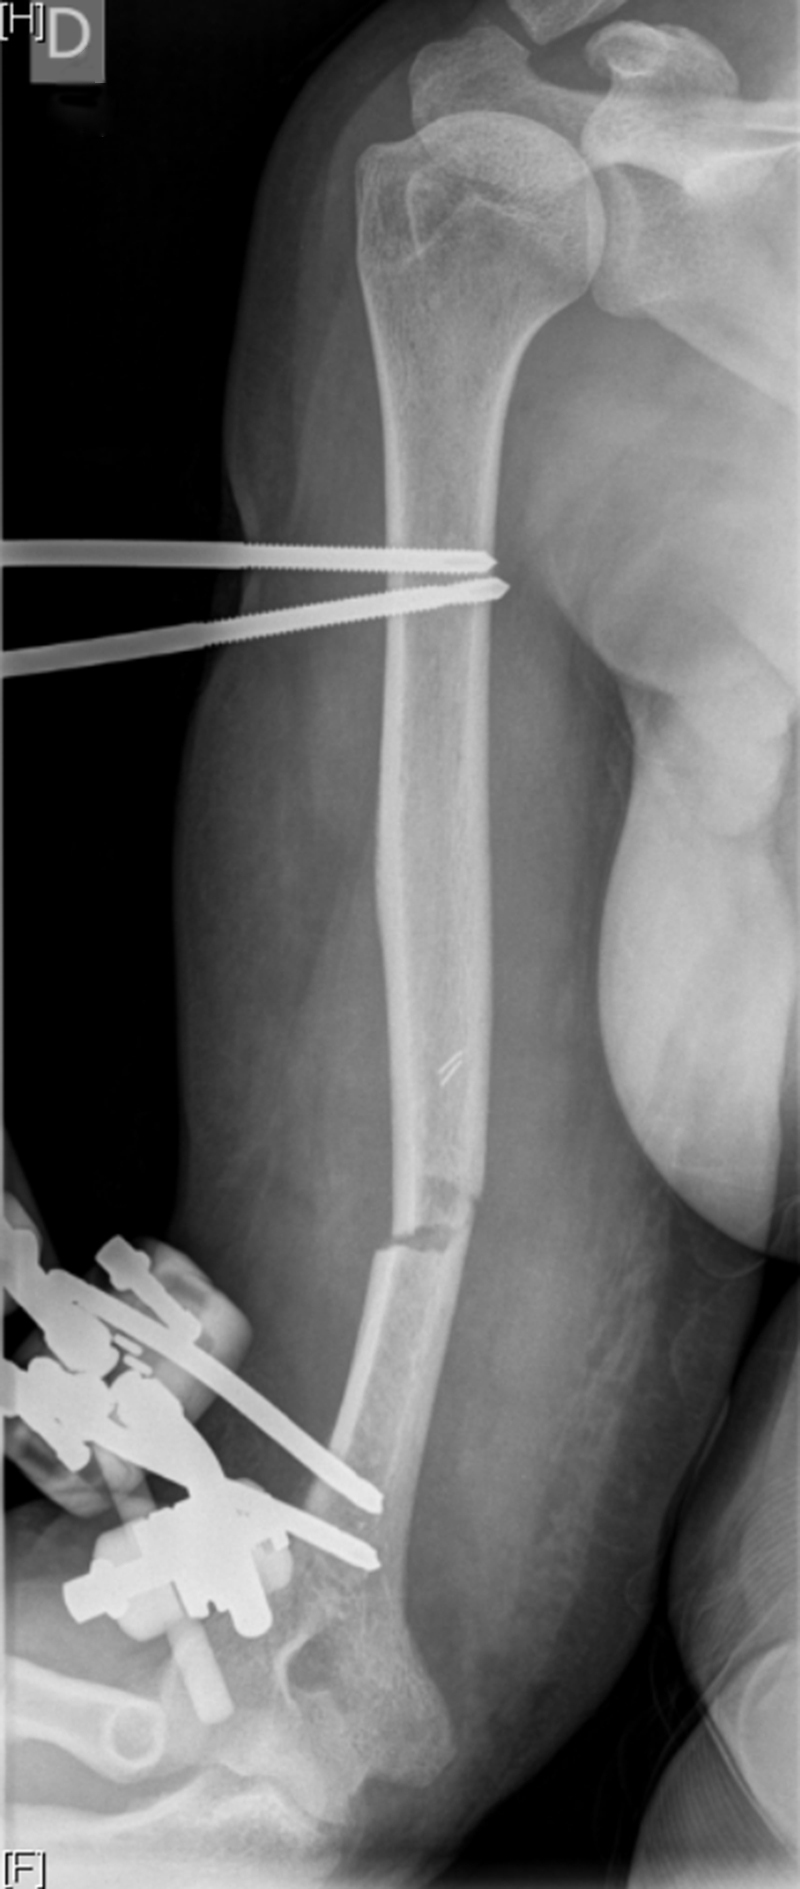

Fig. 2.

Bone radiograph of distal humerus fracture presenting a Cauchoix and Duparc type 3 fracture at her admission.

On the fifteenth day of her hospitalization, and despite antibiotherapy, she developed a purulent discharge from the posterolateral surface of the right arm. Bone samples obtained from surgical biopsies tested negative for bacterial pathogens, but fungal cultures grew for S. cerevisiae. Antifungal susceptibility testing, using the E-test assay, of this S. cerevisiae isolate showed low MICs for itraconazole (0.12 mg/L), fluconazole (4 mg/L), voriconazole (0.06 mg/L) and, amphotericin B (0.25 mg/L) and relatively higher MIC for posaconazole (0.25 mg/L). She was treated with hyperbaric oxygen therapy, voriconazole 250 mg twice daily orally and antibacterial therapy. Imipenem-cilastatin and oral ciprofloxacin were continued. The clinical outcome was favorable with the disappearance of purulent wound drainage (Fig. 3) and she was discharged 25 days after her admission. Overall, she was treated with three months of antibacterials and nine months of voriconazole. An adjunctive treatment with hyperbaric oxygen therapy was performed. The skin had healed after six weeks. External fixation was removed after six weeks with a humeral nonunion repair by double external fixation (Fig. 4).

Fig. 4.

Bone radiograph of distal humerus on 25 days after admission.